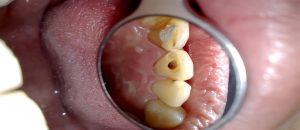

Jurnalikanews– Sering kali, rasa nyut-nyutan akibat gigi berlubang dianggap sebagai “Risiko hobi makan manis.” Selama nyerinya masih bisa diredakan dengan obat pereda nyeri yang dibeli di warung, banyak orang memilih menunda kunjungan ke dokter gigi. Padahal, secara medis, membiarkan gigi berlubang tanpa penanganan bukanlah hal sepele. Kondisi ini ibarat menyimpan masalah yang perlahan bisa berkembang menjadi lebih serius. Lalu, bagaimana mungkin masalah pada gigi bisa mengancam nyawa? Perlu dipahami bahwa gigi bukanlah benda mati. Di dalamnya terdapat jaringan lunak bernama pulpa yang berisi saraf dan pembuluh darah. Ketika lubang (karies) mencapai area ini, bakteri memiliki “jalan tol” untuk masuk ke aliran darah dan menyebar ke organ lain. Jika infeksi gigi dibiarkan berkembang, risikonya tidak hanya sebatas nyeri atau bengkak di area mulut. Dalam kondisi tertentu, komplikasi yang muncul bisa berujung fatal. Berikut beberapa komplikasi fatal yang dapat terjadi :